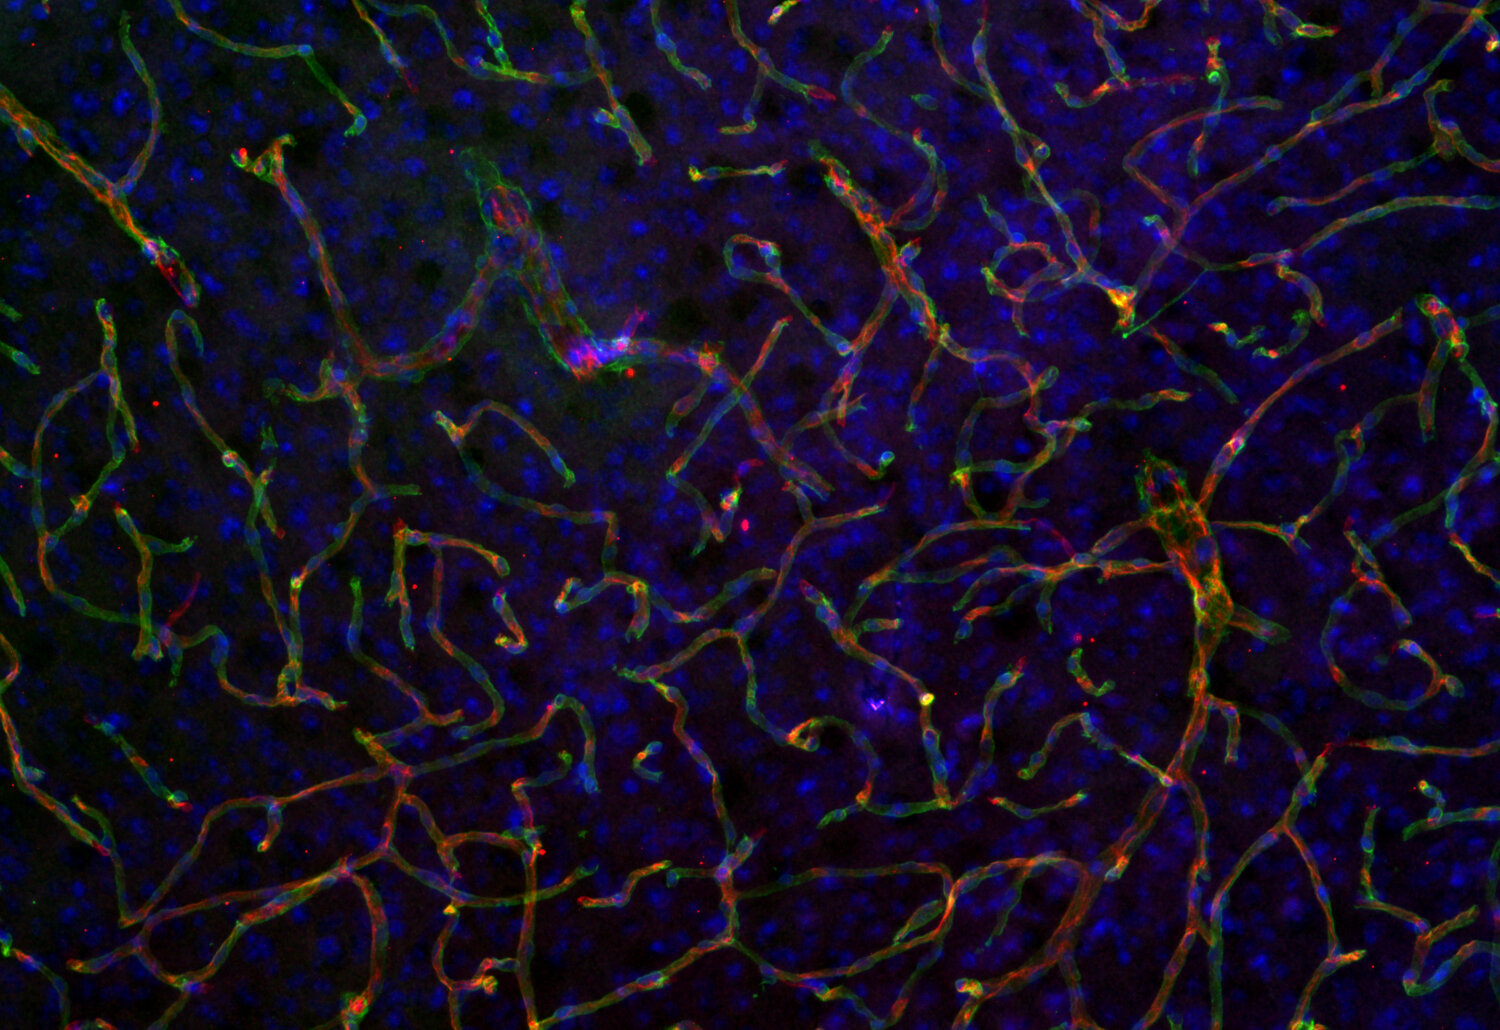

IHC: 1 : 500 up to 1 : 1000 (see remarks) gallery

IHC-Fr: 1 : 500 up to 1 : 1000 (see remarks) gallery

IHC-G: 1 : 500 up to 1 : 1000 (see remarks) gallery

Immunohistochemistry (IHC) on 4% PFA perfusion fixed tissue with 24h PFA post fixation. Immunoreactivity is usually revealed by fluorescence or a chromogenic substrate. Some antibodies require special fixation methods or antigen retrieval steps. For details, please refer to the ”Remarks” section.

Immunohistochemistry on fresh frozen (IHC-Fr) cryo-tissue-sections. In contrast to standard PFA perfusion fixed tissues, fresh frozen cryo-tissue-sections can be variably postfixed with alcohols, acetone or PFA. Alcohol or acetone fixation is e.g. of advantage for antigens masked by PFA crosslinking. For recommended postfixation, please refer to the ”Remarks” section. Immunoreactivity is usually revealed by fluorescence or a chromogenic substrate.

Immunohistochemistry on glyoxal fixed (IHC-G) tissue. The tissue is perfused with saline and afterwards immersion fixed with a glyoxal solution. For details of the glyoxal solution, please refer to the remarks section. Immunoreactivity is usually revealed by fluorescence.